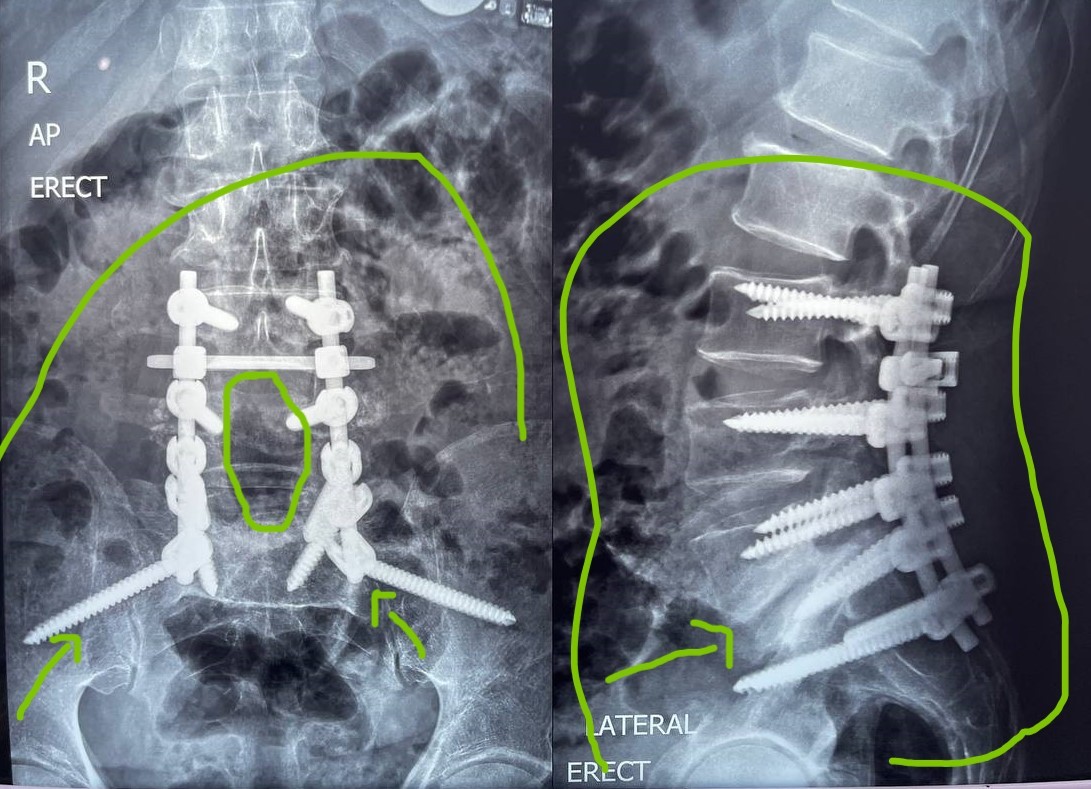

التزحزح الفقاري هو حالة طبية تحدث عندما تنزلق إحدى الفقرات عن مكانها الطبيعي في العمود الفقري. قد يكون هذا الانزلاق بسيطًا أو شديدًا، وقد يتسبب في ضغط على الأعصاب المحيطة ويؤدي إلى آلام في الظهر والساقين.

في العديد من الحالات، يمكن أن يساعد العلاج التحفظي في تخفيف الأعراض وتحسين الحالة. أما في الحالات المتقدمة التي تتطلب الجراحة، فإن العملية الجراحية قد تساعد في استعادة الحركة والحد من الألم بشكل كبير. ومع ذلك، قد يستغرق الشفاء وقتًا، وقد يحتاج المريض إلى متابعة طبية منتظمة.